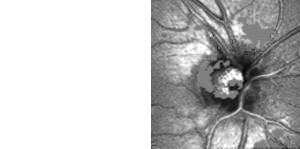

Hilfreich ist das Gerät auch zum Nachweis, zur Quantifizierung und

zur Verlaufskontrolle bei Störungen der Pupillenmotorik von Kindern und

Erwachsenen.